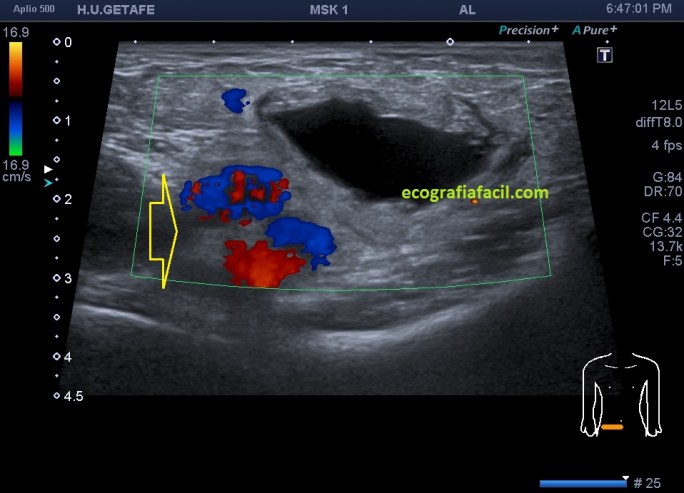

En cuanto localicé este hallazgo realicé corte transverso (imagen 2) y longitudinal (imagen 1), con medidas y estudio en modo doppler para ver vascularización (imagen 3, flecha amarilla), seguidamente, era muy importante asegurar algunas referencias locoregionales como los grandes vasos femorales, siempre debemos documentar esta coexistencia y buscar un cuello que puedes observar con las dos flechas rojas de la imagen 1 y que la ecoestructura marca perfectamente al ser anecoica.

Aunque no muchas, ya había visto alguna vez esta entidad y sabía que era un Quiste de Nuck, pero necesitaba buscar los hallazgos anatómico ecográficos previamente comentados, como la localización junto a los grandes vasos y el cuello, para poder presentarlo a la radióloga para que realizase el informe, que corroboró lo que pensaba, lo cual no tiene relevancia alguna. Esta patología puede ser conocida también como Hidrocele de Nuck.